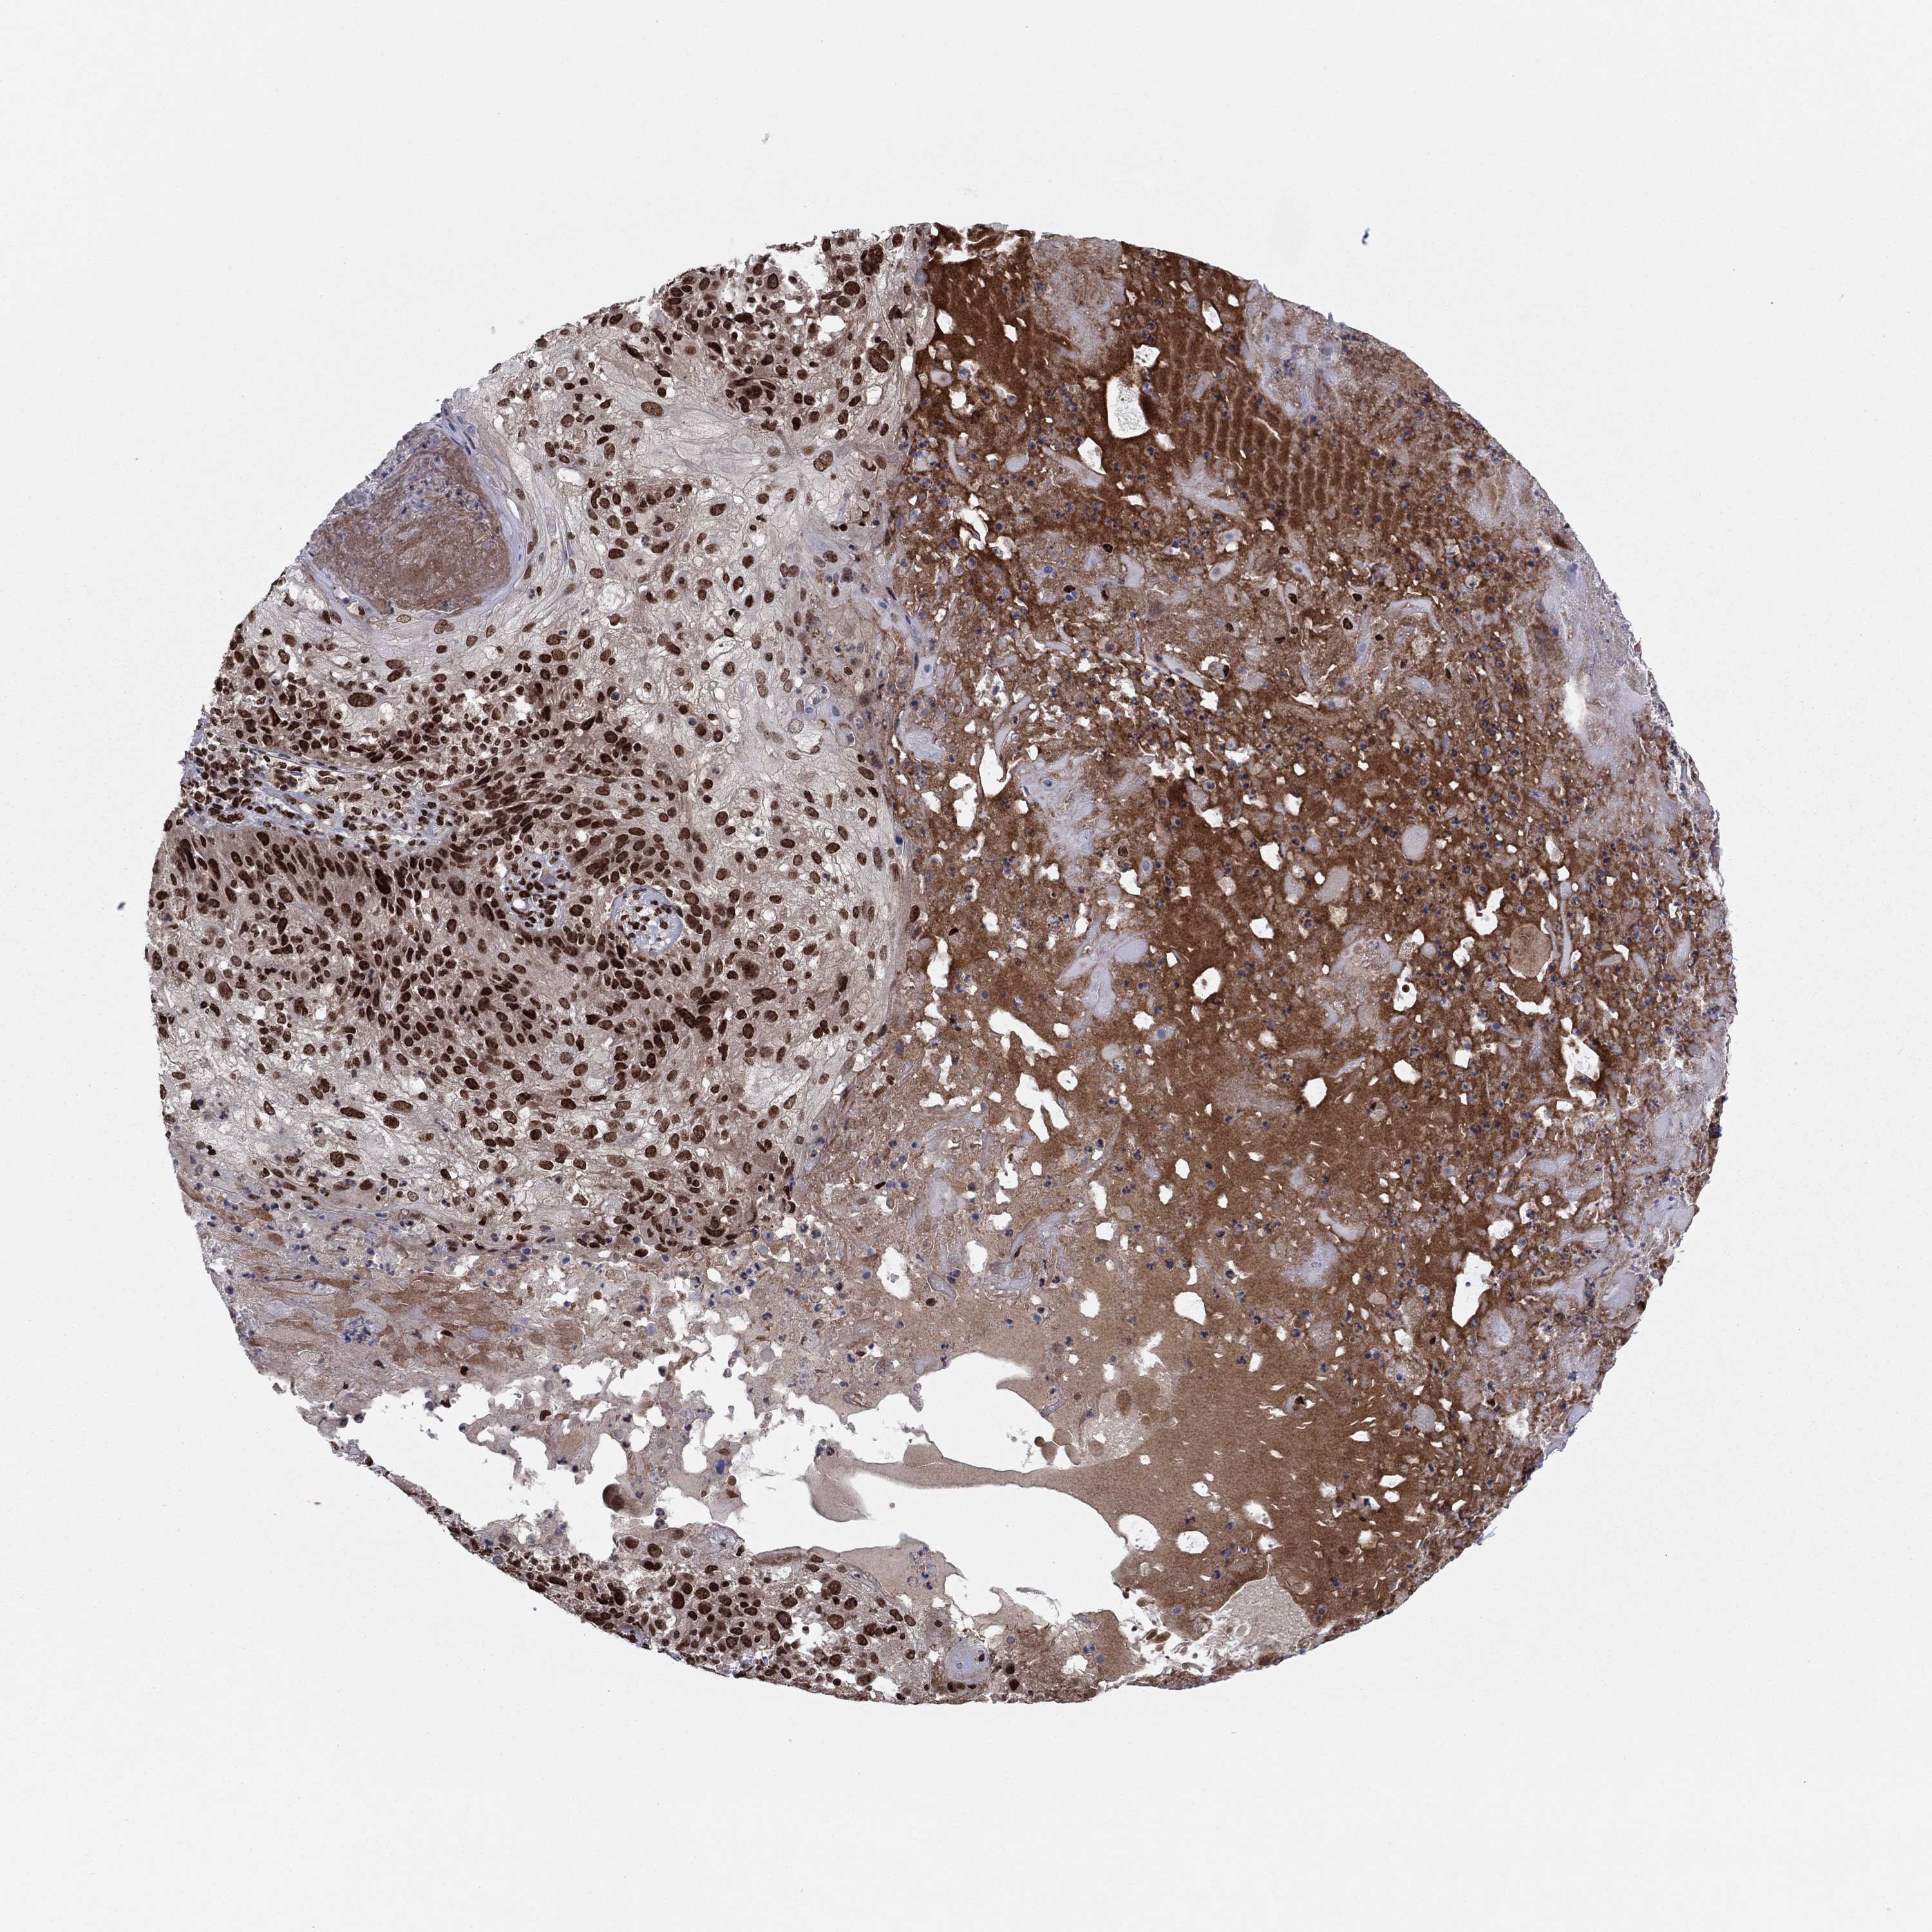

Basal cell and squamous cell cancer

SKIN CANCER - Protein expressioni

A mouse-over function shows sample information and annotation data. Click on an image to view it in a full screen mode. Samples can be filtered based on level of antibody staining by selecting one or several of the following categories: high, medium, low and not detected. The assay and annotation is described here.

Each image is clickable and will lead to virtual microscopy that enables deeper exploration of all samples and also displays staining intensity scores, fraction scores and subcellular localization as well as patient and tissue information for each sample.

Antibody HPA063665

Staining

High

Medium

Low

Not detected

Intensity

Strong

Moderate

Weak

Negative

Quantity

>75%

75%-25%

<25%

None

Location

Nuclear

Cytoplasmic/membranous

Cytoplasmic/membranous,nuclear

Squamous cell carcinoma, NOS